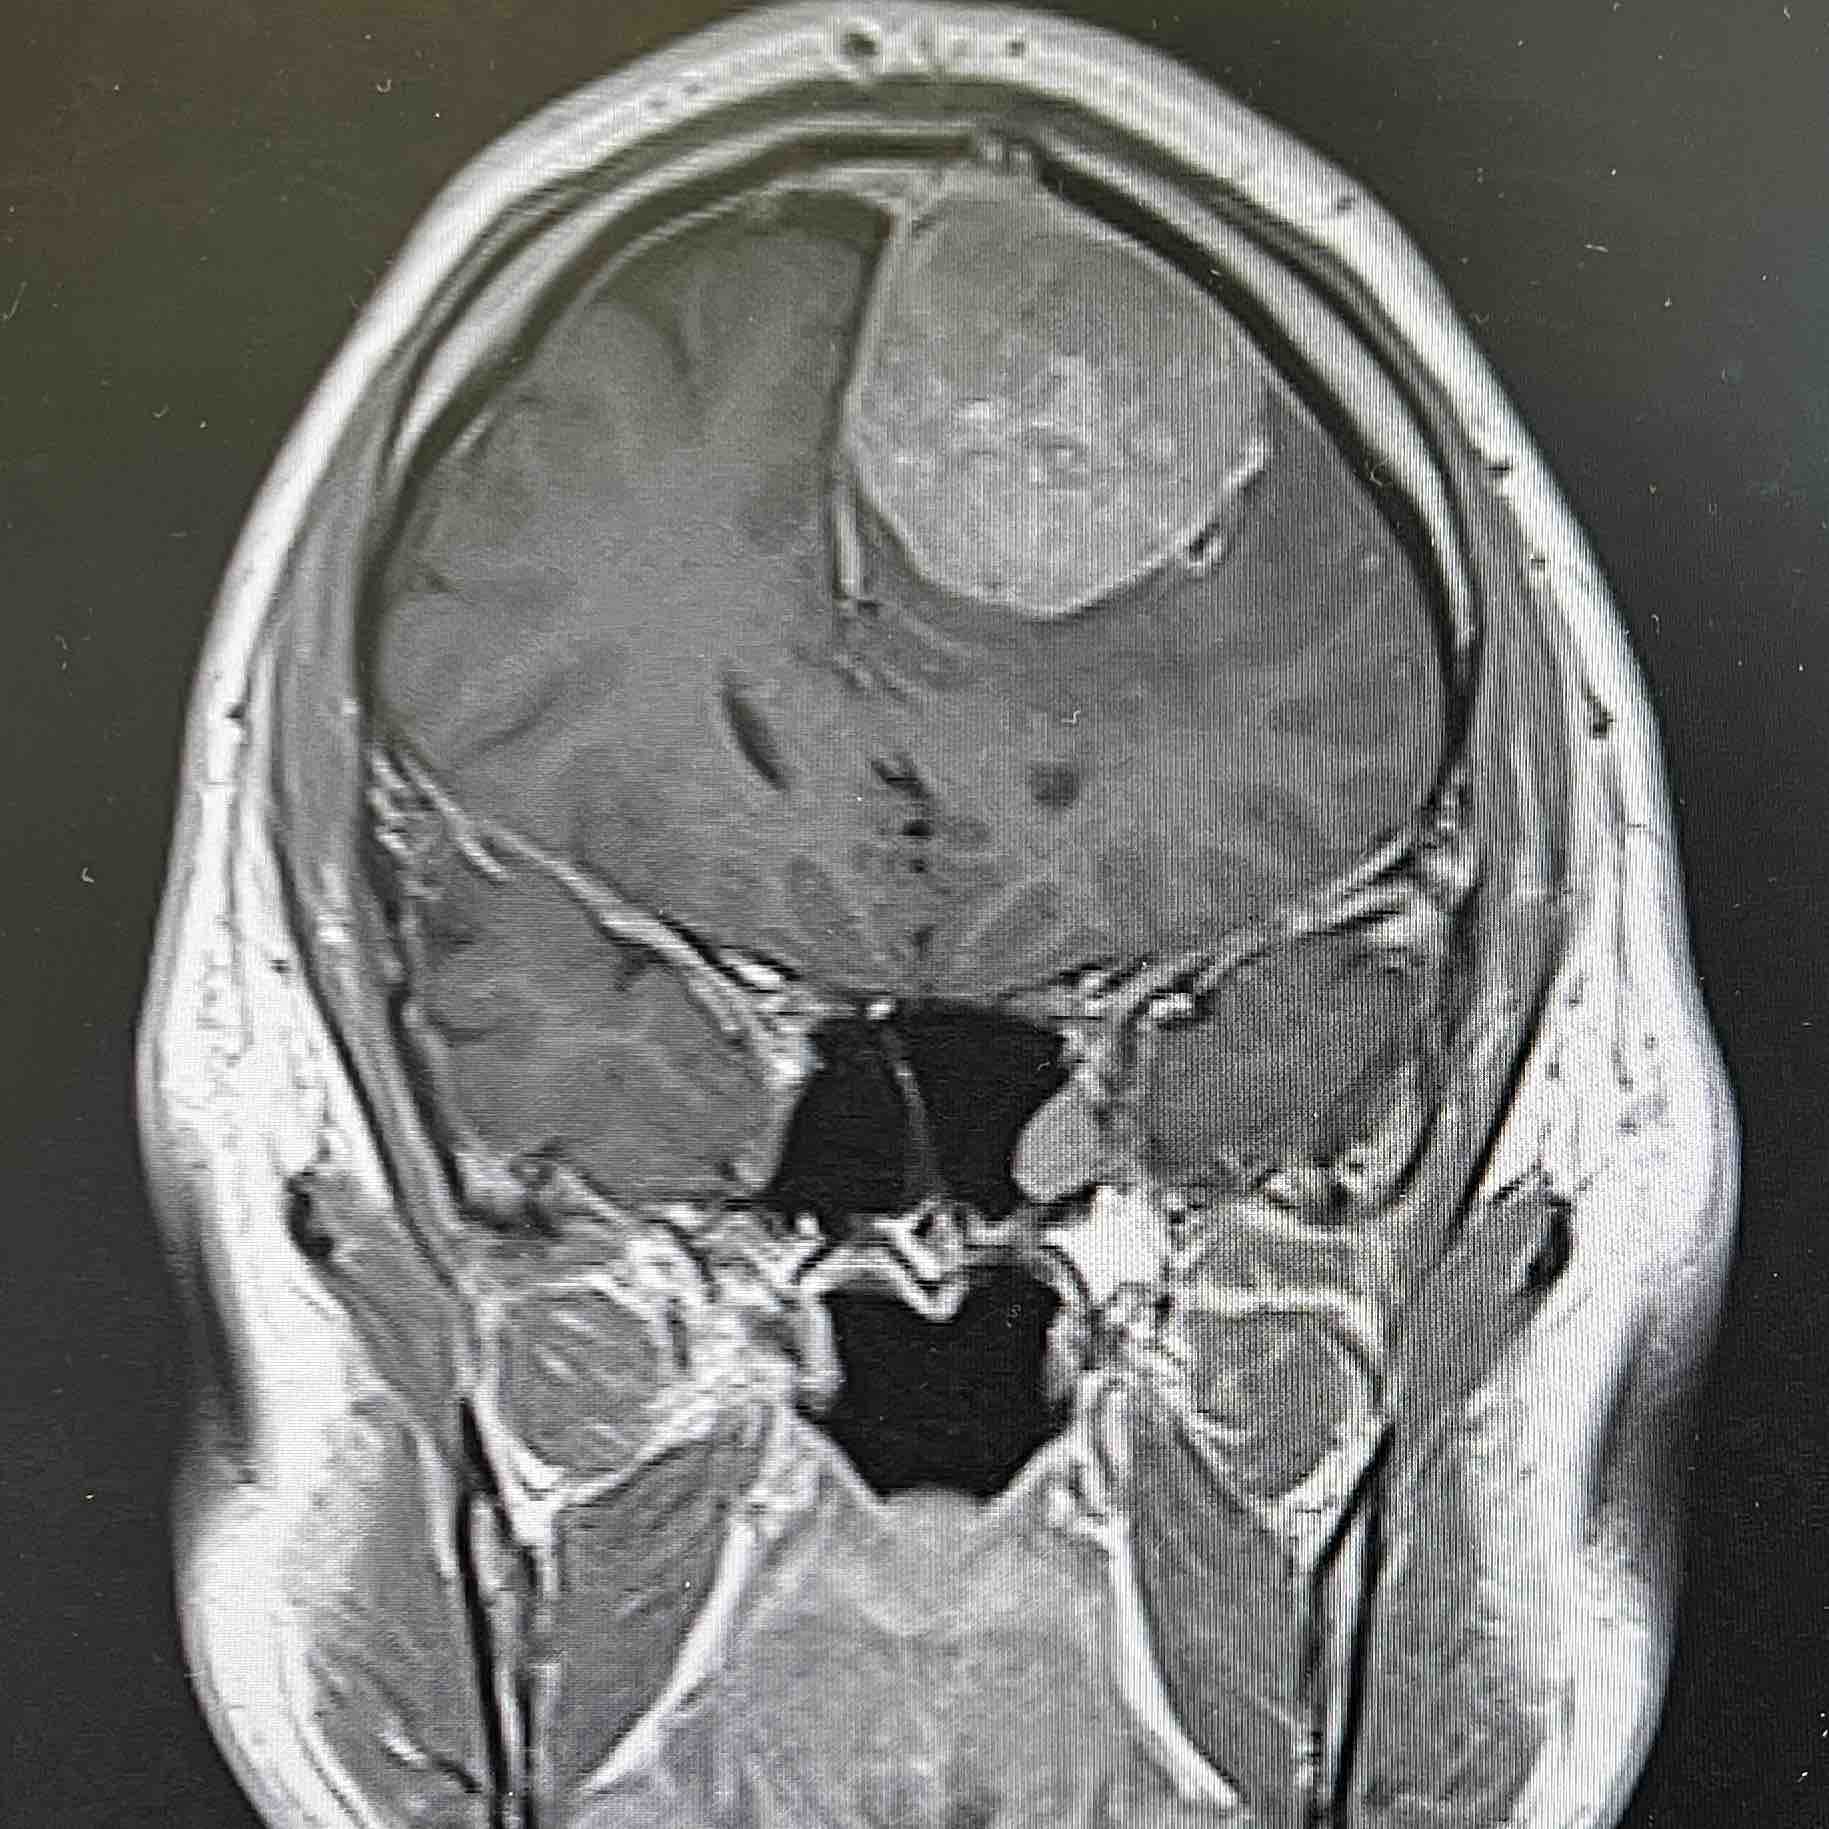

Once in the hospital I was given an MRI where

the neurological team fond a 5x4x4 cm tumor growing inside my left frontal lobe with current blood flow.

The pressure has been extensive and is around 15-20 years old according to the bruised aera and size on the scan.

The mass is not cosmetic or something that can be left untreated. It must have action taken now for my health. .

I have a tumor the size of a small lime to a tennis ball pressing on my left frontal lobe that must come out and I need some confidence it will come out.